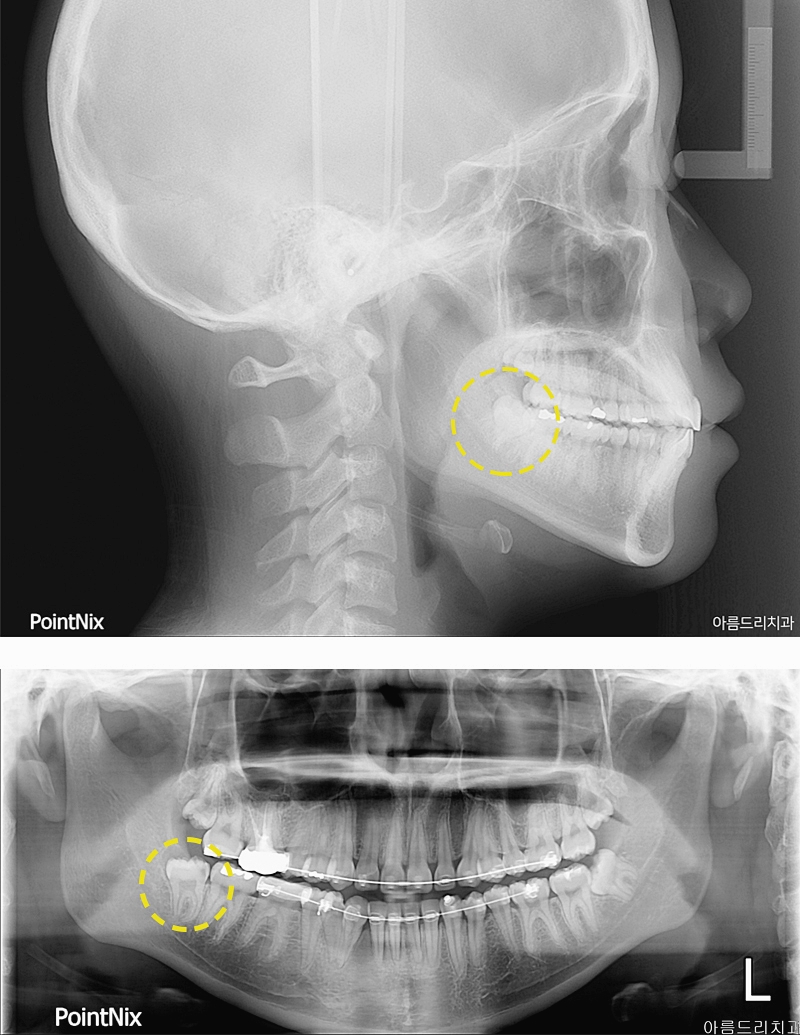

매복사랑니는 치아의 맹출이 이루어지지 않고 사랑니가 잇몸 밖으로 나오지 못해 누워있거나 숨은 상태를 보이는 치아를 이야기해요. 보통 턱뼈의 크기가 작아 치열가 배열된 공간이 부족하거나 치아의 배열이 올바르지 못할 경우에 발생을 하는데요. 평소에 맨 눈으로 쉽게 확인을 할 수 없으며 일상생활에 있어 불편함을 느끼게 하거나 통증과 염증을 유발하기도 했었어요. 아름드리치과에 내원한 환자분의 경우 정상적이지 않는 각도로 자리잡은 매복사랑니발치를 하지 않은 경우에는 주변 치아의 신경을 건드리며 자랄 수 있어 인접치에 안 좋은 영향을 줄 수 있었어요. 특히 비스듬하거나 누워 자라는 매복 사랑니는 잇몸에 염증을 유발하여 치열에 문제를 일으킬 수 있었어요. 치아 머리만 나와 있는 매복 사랑니의 모습이라면 제대로 구강 관리를 하기 힘들어 음식물이 고이기 때문에 치주염과 치아 우식증, 구취등의 문제도 발생하게 되는데요. 컨디션의 저하에 따라 잇몸이 붓고 매복사랑니통증이 느껴지기도 한다면 발치가 효율적일 수 있겠어요.

아름드리치과에서 말하는 매복사랑니발치는 환자마다 맹출 형태가 다르기에 더욱 신중하게 접근해야하는 수술이었어요. 매복되어 있는 정도에 따라 뽑는 방식에도 차이점이 생기기 때문이에요. 치아의 머리가 일부분만 들어가 있는 단순 매복의 경우에는 잇몸만 절개하여 발치를 진행하고 잇몸 안에 부분적으로 치아 머리가 숨어있거나 골 안에 묻혀 있는 복합 매복사랑니라면 잇몸 절개와 더불어 치아를 분리하여 발치를 진행해 주어야 했었어요. 완전 매복의 경우에는 매복사랑니발치 가운데 가장 고난이도라고 보는 수술이에요. 매복된 깊이가 깊기 때문에 정확한 검진을 기반으로 복잡한 단계를 거쳐 빼내야 하고 치아를 조각 내어 분리해야 하는 경우도 발생할 수 있었었어요. 골 삭제도 필요하기에 발치 과정에서 여러 치과 시술을 동시에 진행하는 것으로 아름드리치과와 같은 임상 경험이 풍부한 병원에서 진행하시는걸 추천드려요. 매복사랑니는 치신경에 인접해 있기 때문에 일반적인 사랑치를 발치하는 것보다 더 까다롭게 진행되는 시술이었어요. 발치 시 신경을 건드리면 부분 마비의 위험도 생기기 때문에 더욱 정밀한 진료가 동반되어야 하기에 사전에 정확한 검진을 통해 영구치의 정확한 상태와 위치까지 파악하여 치료 계획을 수립하는 것이 필요했었어요. 신경조직과 가깝기에 발치를 미룬다면 나이가 들수록 턱뼈가 약해지면서 합병증의 발생 가능성도 높아진다는걸 염두해 두셨어야 했었어요. 모든 사랑니가 마찬가지이지만 눈에 보이지 않는 매복사랑니통증이 느껴지신다면 초기에 치료 계획을 수립하는 것이 옳은 선택일 수 있었어요.